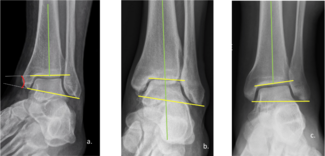

A. Douglas Spitalny, DPM, FACFAS

This author presents several case studies showing the influence of ankle deformities.